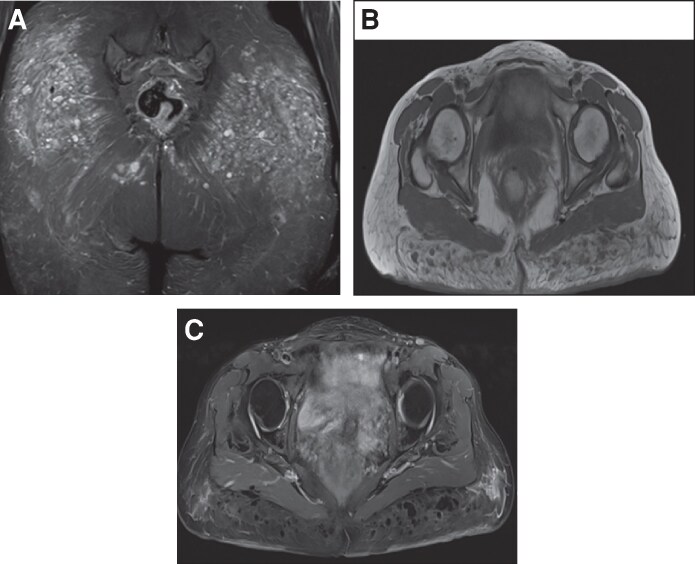

生物聚合物经常用于美学或重建目的,通常没有充分考虑它们可能引起的潜在的长期健康并发症。这些物质的使用与佐剂诱导的自身免疫/自身炎症综合征(ASIA综合征)有关;然而,现有文献有限,目前对其管理尚无明确的共识。本病例报告旨在描述一个诊断为类风湿关节炎的患者中严重的生物聚合物诱导炎症性疾病的病例,强调诊断和治疗方法。本病例报告检查了一名58岁女性患者,20年前曾在臀部和面部区域应用生物聚合物,过去2年诊断为类风湿关节炎。她表现为严重的炎症性皮肤病变,伴有关节痛的恶化。MRI扫描显示外源性物质伴周围组织严重炎症征象,活检符合“瑞士奶酪”形态的异物肉芽肿。患者住院并接受多学科治疗,取得了良好的临床疗效。本病例强调了对自身免疫性疾病和既往接触过生物聚合物的患者进行综合评估和多学科方法的重要性。自身免疫性疾病的共存可加重炎症反应,提示需要进一步研究这种相互作用及其预后影响。证据等级:5(风险)。

Biopolymers are frequently used for aesthetic or reconstructive purposes, often without adequate consideration of the potential long-term health complications they may cause. The use of these substances has been associated with autoimmune/autoinflammatory syndrome induced by adjuvants (ASIA syndrome); however, the existing literature is limited, and there is currently no clear consensus regarding its management. This case report aims to describe a case of severe biopolymer-induced inflammatory disease in a patient with a diagnosis of rheumatoid arthritis, highlighting both the diagnostic and therapeutic approaches. This case report examines a 58-year-old female patient with a history of biopolymer application to the gluteal and facial region 20 years before and a diagnosis of rheumatoid arthritis for the past 2 years. She presented with severe inflammatory skin lesions with worsening arthralgia. An MRI scan revealed exogenous material with signs of severe inflammation of the surrounding tissues, and a biopsy was consistent with foreign body granulomas with a "Swiss cheese" morphology. The patient was hospitalized and received multidisciplinary management, achieving an excellent clinical response. This case highlights the importance of a comprehensive evaluation and a multidisciplinary approach in patients with autoimmune disease and previous exposure to biopolymers. The coexistence of autoimmune diseases can aggravate the inflammatory response, suggesting the need for additional studies exploring this interaction and its prognostic impact. Level of Evidence: 5 (Risk).